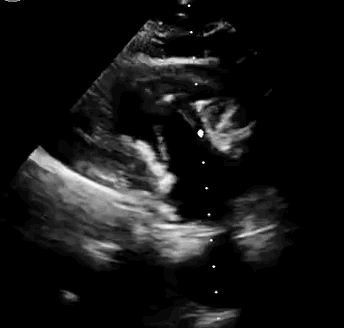

上海中山醫(yī)院葛均波院士、錢(qián)菊英院長(zhǎng)、周達(dá)新教授、潘文志教授、潘翠珍教授、李偉教授共同完成此次臨床前研究。術(shù)后葛均波院士對(duì)Lux-Valve Plus的器械操作性能給予了高度評(píng)價(jià),DSA和超聲影像也顯示出在本次研究中Lux-Valve Plus的安全性和有效性俱佳。

本次臨床前研究經(jīng)右側(cè)頸靜脈置入LuX-Valve Plus輸送系統(tǒng)可調(diào)彎鞘管,在DSA及超聲引導(dǎo)下將人工三尖瓣瓣膜植入到原有三尖瓣位置,利用獨(dú)特的錨定技術(shù)將人工瓣膜支架可靠固定在預(yù)定的位置。